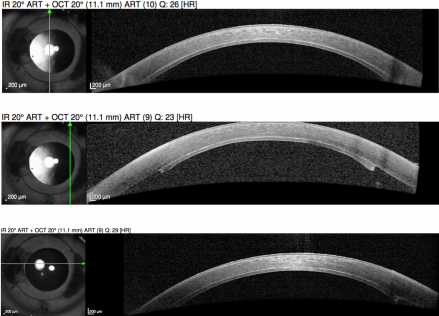

- Graft detachment: Anterior segment OCT can assess for graft detachments. Fig. 2. If the graft is detached, it will need to be reattached by rebubbling the anterior chamber. Since the graft has been in aqueous fluid, it often works well after reattachment. [19]